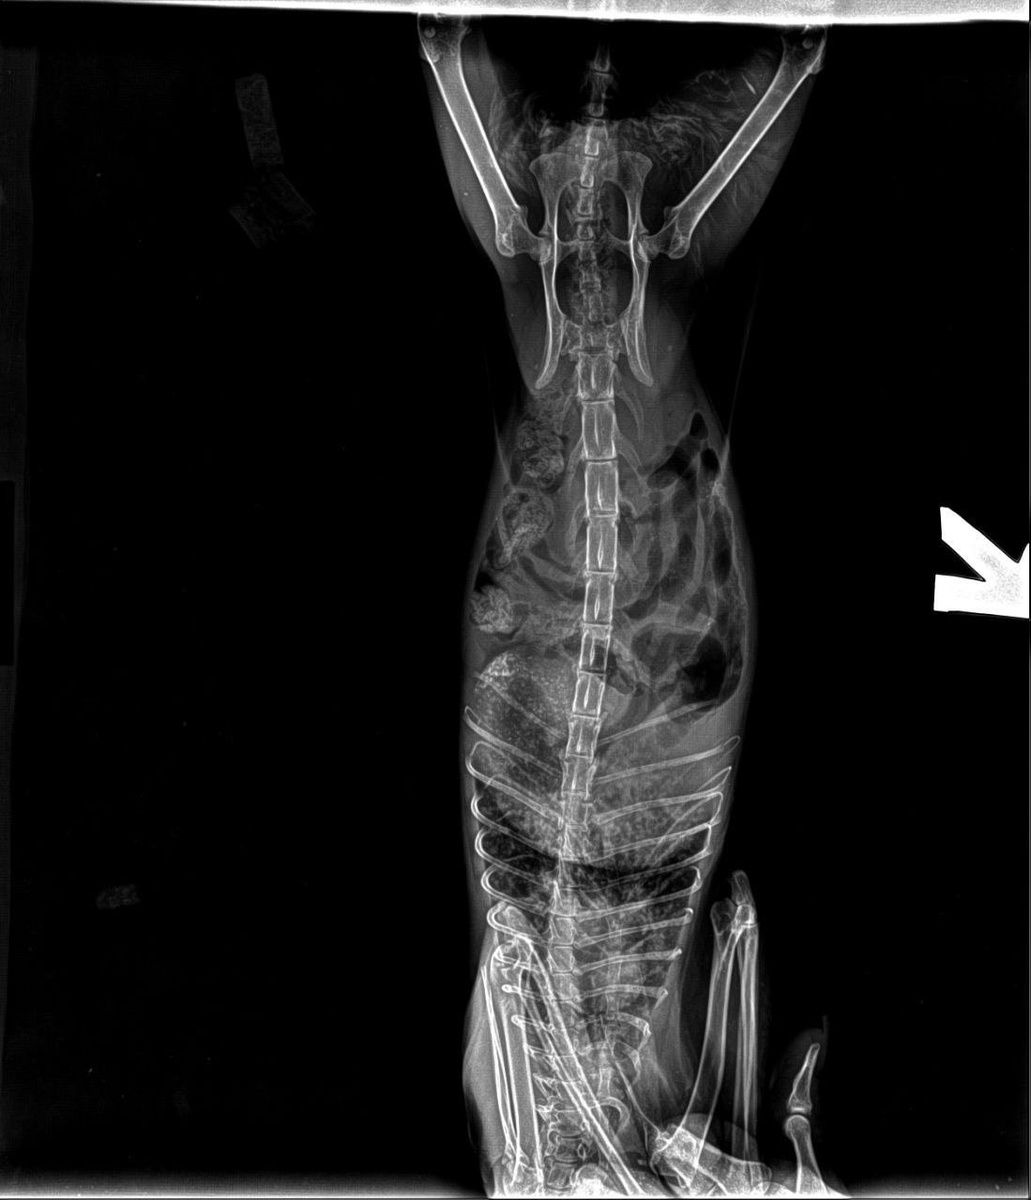

Вместо мифического генетического отростка, который якобы парализовал кошку и стал поводом для предложений об усыплении, нормальный рентген показал суровую реальность: никакой генетики там нет, зато есть глубокая болевая чувствительность и последствия встречи с автомобилем, который в этом поединке оказался прочнее. Весь этот псевдомедицинский бред про анатомические аномалии рассыпается о физиологию — у Августы просто серьезный ушиб и сильная компрессия, так что вместо эвтаназии мы будем разбираться, как вернуть это «безе» на четыре лапы.

Планы простые, как кирпич: ждем, пока спадет компрессия. Встанет или не встанет — вопрос к мирозданию, но Августа ест с аппетитом терминатора, а значит, сдаваться не планирует. Нам нужны лезвия для машинки (брить котиков нынче нечем) и ресурсы на анализы, УЗИ и бесконечные пеленки.